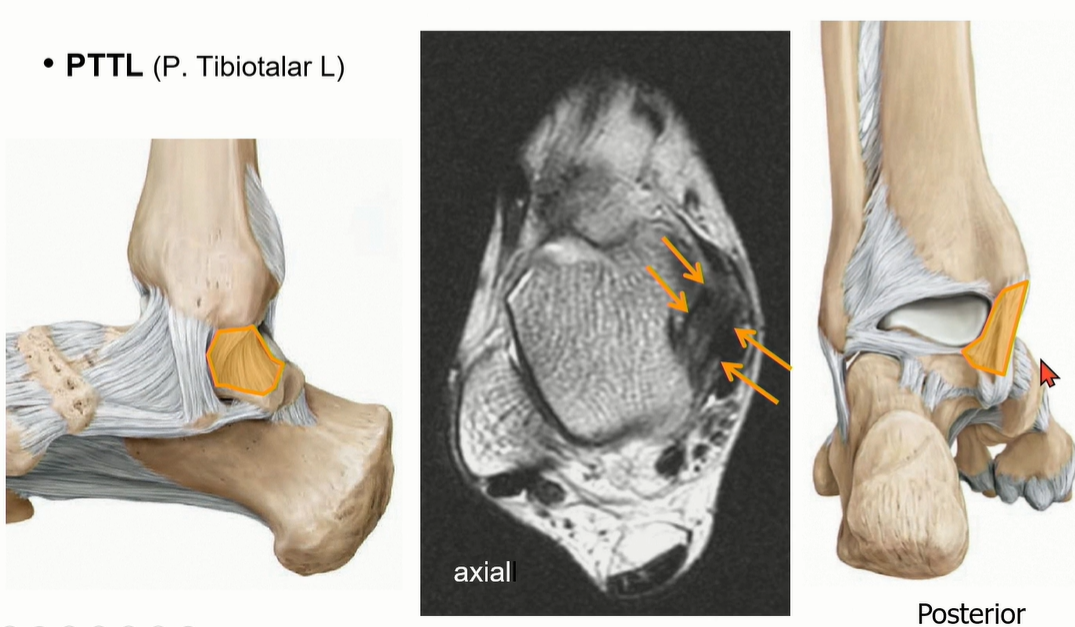

Deep deltoid liagment의 하나인 PTTL의 주행.

ATTL에 비해서 넓어서 영상에서 확인이 용이하다. ligament 사이에 fat이 관찰되는 것이 정상.

coronal cut에서도 fat때문에 straiation이 보이는 것이 정상이다.

녹색으로 표시한 것은 flexor retinaculum으로 deltoid ligament와 오인하지 않도록 조심해야 한다.